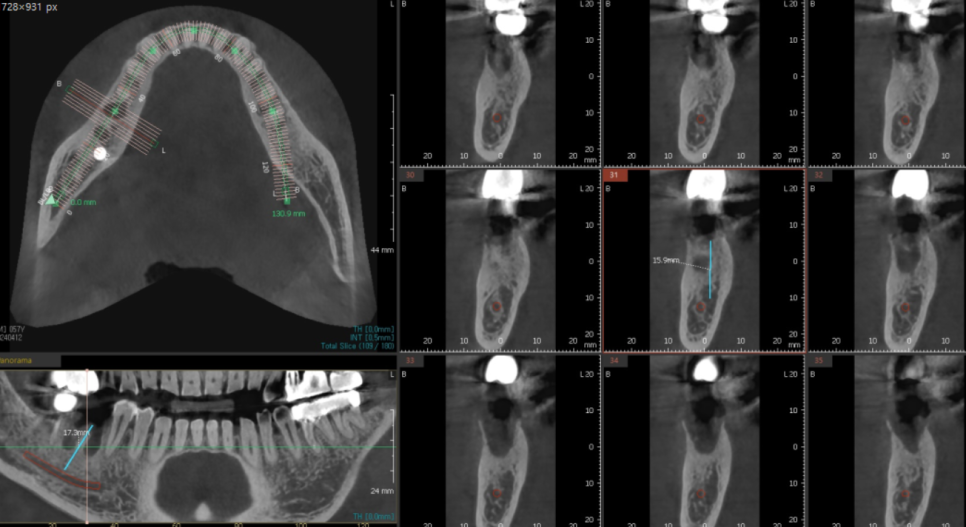

24.04.12

발치 후에 상태를 확인하기 위해

ct를 찍어보았는데요.

뼈가 많이 녹아있어서

2달 후 어느정도 뼈가 차오르면

그때 미사역 임플란트를 심기로 결정하였습니다.